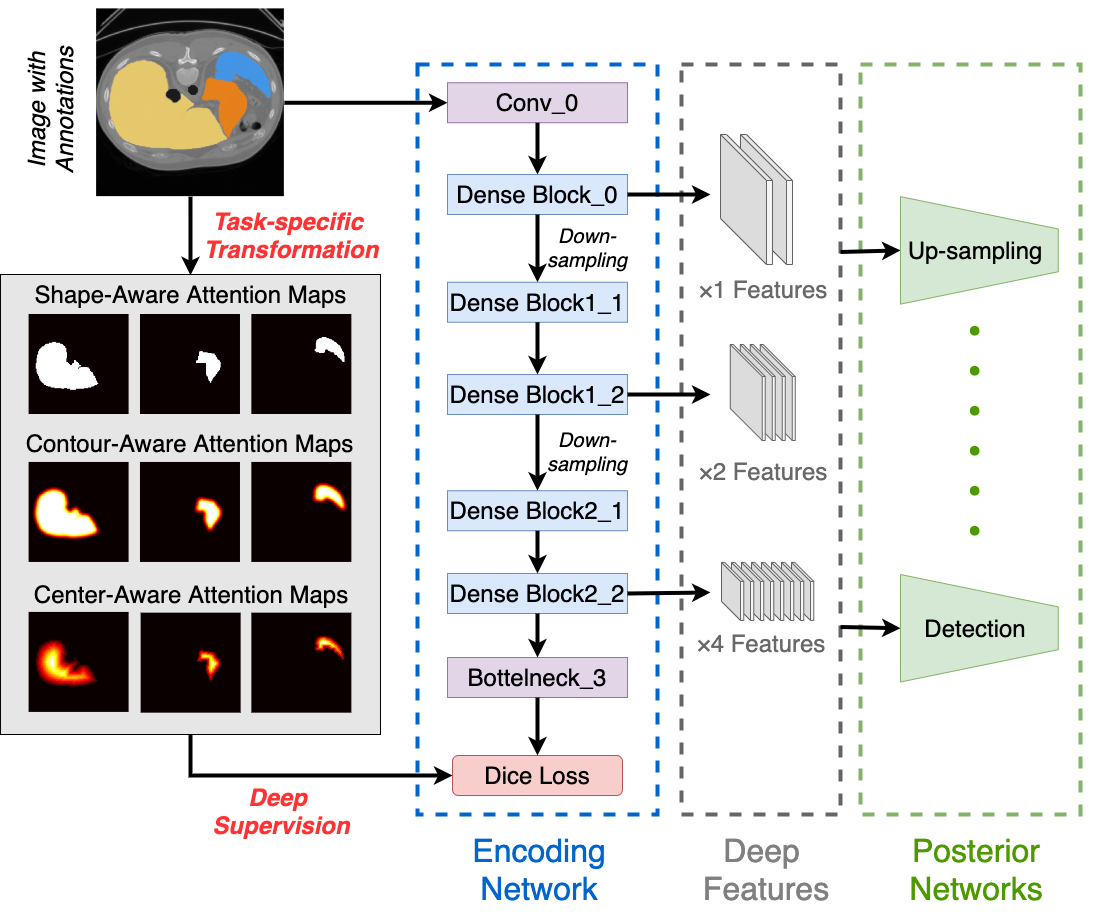

2.2 Generation of the Attention Map

The attention map [3] has been widely used in semantic segmentation models to improve the learning ability by establishing connections between different locations in the feature map. In T-Net, we utilize the attention map in a different way by taking it as deep supervisions to train the feature extractor. In this paper, we propose three ways to obtain the attention maps from pixel-wise annotations, enabling the encoding network to pay attention to different areas of the recognition target. Examples of different attention-maps used in this paper can be seen in Fig. 2. To be noted, the template generation is not limited to these three methods. We can also deploy other types of attention maps for supervision, depending on applications.

2.2.1 Shape-Aware Attention Map

The basic attention map should play the same role as in a conventional encoder-decoder network, where the feature extractor focuses merely on the object shape. Therefore, we directly down-sample the binary mask of the recognition target with nearest-neighbour interpolation, which can guarantee each pixel value in the attention map is either 0 or 1.

2.2.2 Contour-Aware Attention Map

To make the encoding network pay additional attention to the area outside the boundary of targets, we expand the shape-aware attention map by applying a normalized Gaussian filter. The Gaussian filter can make a smooth transition from foreground to background on the object boundary and the normalization can guarantee the pixel value is between 0 and 1.

2.2.3 Center-Aware Attention Map

To encourage the encoding network to focus on the object center, we transform the shape-aware attention map into a normalized distance map, where each pixel value inside the object reflects the distance between it and the object boundary. For normalization, we divide the distance map by the largest distance value, which should belong to the center point as it is most far away from the background.

2.3 Network Architecture

In this section, we introduce the detailed architecture of T-Net. As shown in Fig. 2, the framework consists of an encoding network to learn feature representations and multiple posterior networks for different analysis tasks. The encoding network is optimized by attention maps generated by different methods according to the specific task, and the posterior networks are trained with multi-level features generated from the encoding network.

2.3.1 Encoding Network

We use dense block [4] as our backbone to learn different levels of deep features in the encoding network. As shown in the blue box in Fig. 2, the encoding network has two steps of down-sampling to extract features. The layer on the top maps the input image into fixed-number feature maps. Then features are generated from the first dense block, while and features are obtained from two consecutive dense blocks after a layer. Finally, the features are reduced to channels by a layer, which consists of an layer and a layer.

2.3.2 Posterior Networks

The architecture of a posterior network depends on the kind of task in image analysis. For example, the posterior network should be an up-sampling network for segmentation and regression network for detection. To be noted, under a segmentation task, T-Net is still different from a general encoding-decoding network as the two networks in T-Net are trained separately.